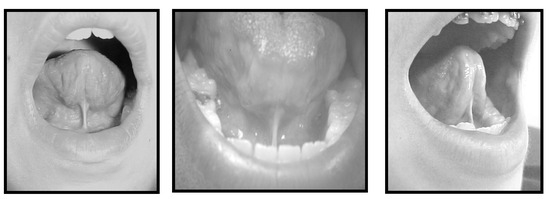

Two speech therapists evaluated the frenulum and characterized it as normal or altered using the qualitative protocol proposed by Marchesan (2004) according to the following criteria: a) short or smaller than most frenulum, although inserted correctly (Moore & Dalley, 2001) at the halfway back area on the undersurface of the tongue and extending to the floor of the mouth (Singh & Kent, 2000) (Figure 1); b) with anterior insertion, demonstrating normal size while being inserted at any point forward from the halfway area along the underside of the tongue; it may be inserted close to the apex (Figure 2); c) short with anterior insertion, this being a mix of the previous two (Figure 3).

Figure 1. Short Frenulum.

Figure 2. Frenulum with Anterior Insertion.

Figure 3. Frenulum with Anterior Insertion and Short.